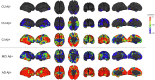

Findings: CU Aβ- participants had very low rates of tau accumulation in the mesial temporal lobe (MTL). In CU Aβ+, significantly higher rate of accumulation was seen in the MTL (particularly the amygdala), extending into the inferior temporal lobes. In MCI Aβ+, the rate of accumulation was greatest in the lateral temporal, parietal and lateral occipital cortex, and plateaued in the MTL. Accumulation was global in AD Aβ+, except for a plateau in the MTL. The eroded subcortical white matter reference region showed no significant advantage over the cerebellar cortex and appeared prone to spill-over in AD participants. Data fitting suggested approximately 15-20 years to accumulate tau to typical AD levels.

Interpretation: Tau accumulation occurs slowly. Rates vary according to brain region, disease stage and tend to plateau at high levels. Rates of tau accumulation are best measured in the MTL and inferior temporal cortex in preclinical AD and in large neocortical areas, in MCI and AD.